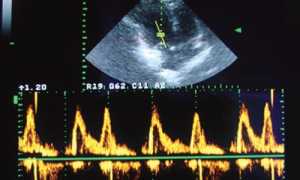

- метод для визуализации просветов. Он помогает выявить наличие бляшек, вероятность закупорки и вероятную скорость кровотока. Называется он дуплексное сканирование ультразвуком;

При наличии сопутствующих патологий может быть проведено еще ультразвуковое исследование или коронография.